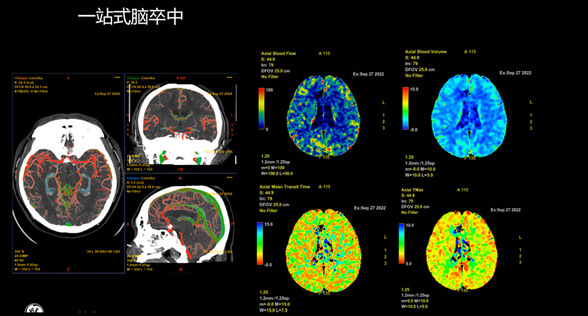

颅脑灌注分析(CTP)检查:通过先进后处理软件,系统快速生成全脑灌注图谱,精准量化核心梗死区与缺血半暗带的大小。结果显示,患者右侧大脑半球虽已出现大面积脑梗死,但仍存在可挽救的缺血半暗带。

这一关键数据的精确测量,为临床医生制定溶栓或取栓方案提供了极具价值的“作战地图”,避免了盲目治疗,极大提升了救治成功率。

CTP检查提示全脑核心梗死区体积为114.6ml,Mismatch体积为180.8ml,低灌注区体积为295.4ml,Mismatch比值为2.6。

2、诊断之准:超高清成像清晰分辨闭塞血管位置,并用色阶图直观显示缺血区域的“核心”与“半暗带”,让医生“看”得见脑组织的存活状态。